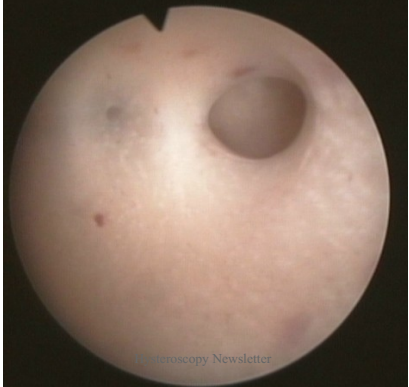

宫腔镜检查:诊断的金标准。宫腔镜可直视宫腔内是否有粘连,评估其严重程度,也可直视正常子宫内膜覆盖宫腔的范围,对疾病预后的评估给予指导。